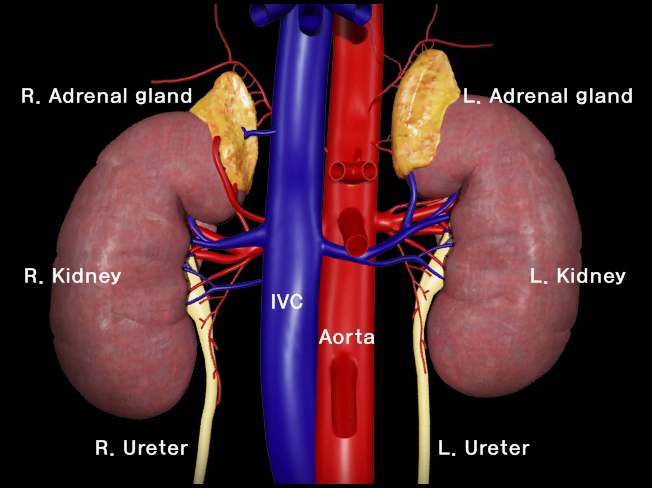

홍보, 학회 발표, 수술 교육, 의학 제품 소개와 관련한 영상을 3D로 제작하여 제공해드립니다.

제작범위 : 신체 전신, 뼈대, 장기, 혈관 등 사람, 동물의 모든 표현이 가능하며, 수술과 관련한 도구 제작도 가능합니다.